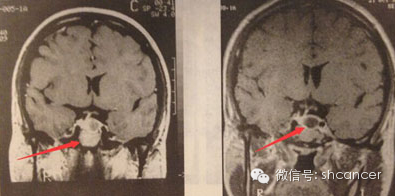

案例二:患者男,38岁,垂体瘤。用伽玛刀治疗1年半以后,肿瘤明显缩小。